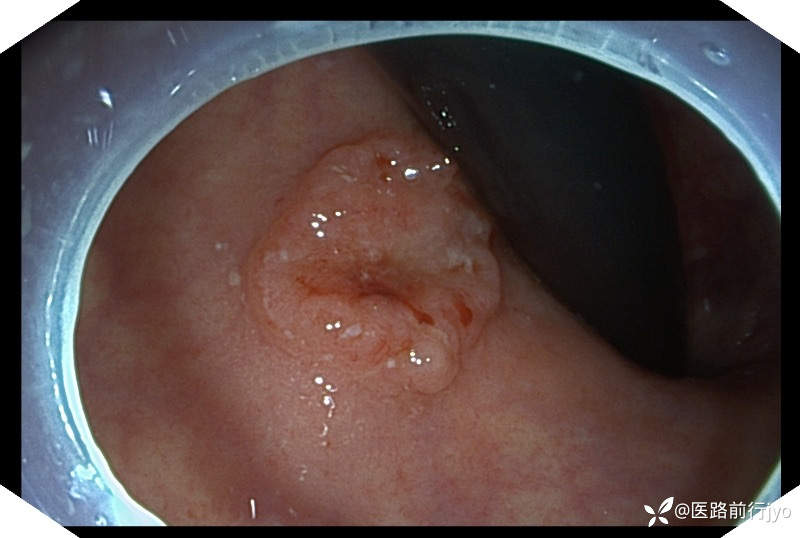

今日上午一例肠镜:患者 女 67岁 患者肠道清洁好,乙状结肠仅发现1枚小息肉,本准备退镜收工,退镜到肛门口突然看到一隆起性小片粘膜,立即倒镜观察考虑直肠早期癌变,距肛周约1cm的大小约1.6cmx1.3cm椭圆形欠规则隆起,中央凹陷伴自发性出血,活捡5块,质脆,易出血。考虑诊断:直肠粘膜不规则(11a+11c)隆起(考虑直肠癌可能)